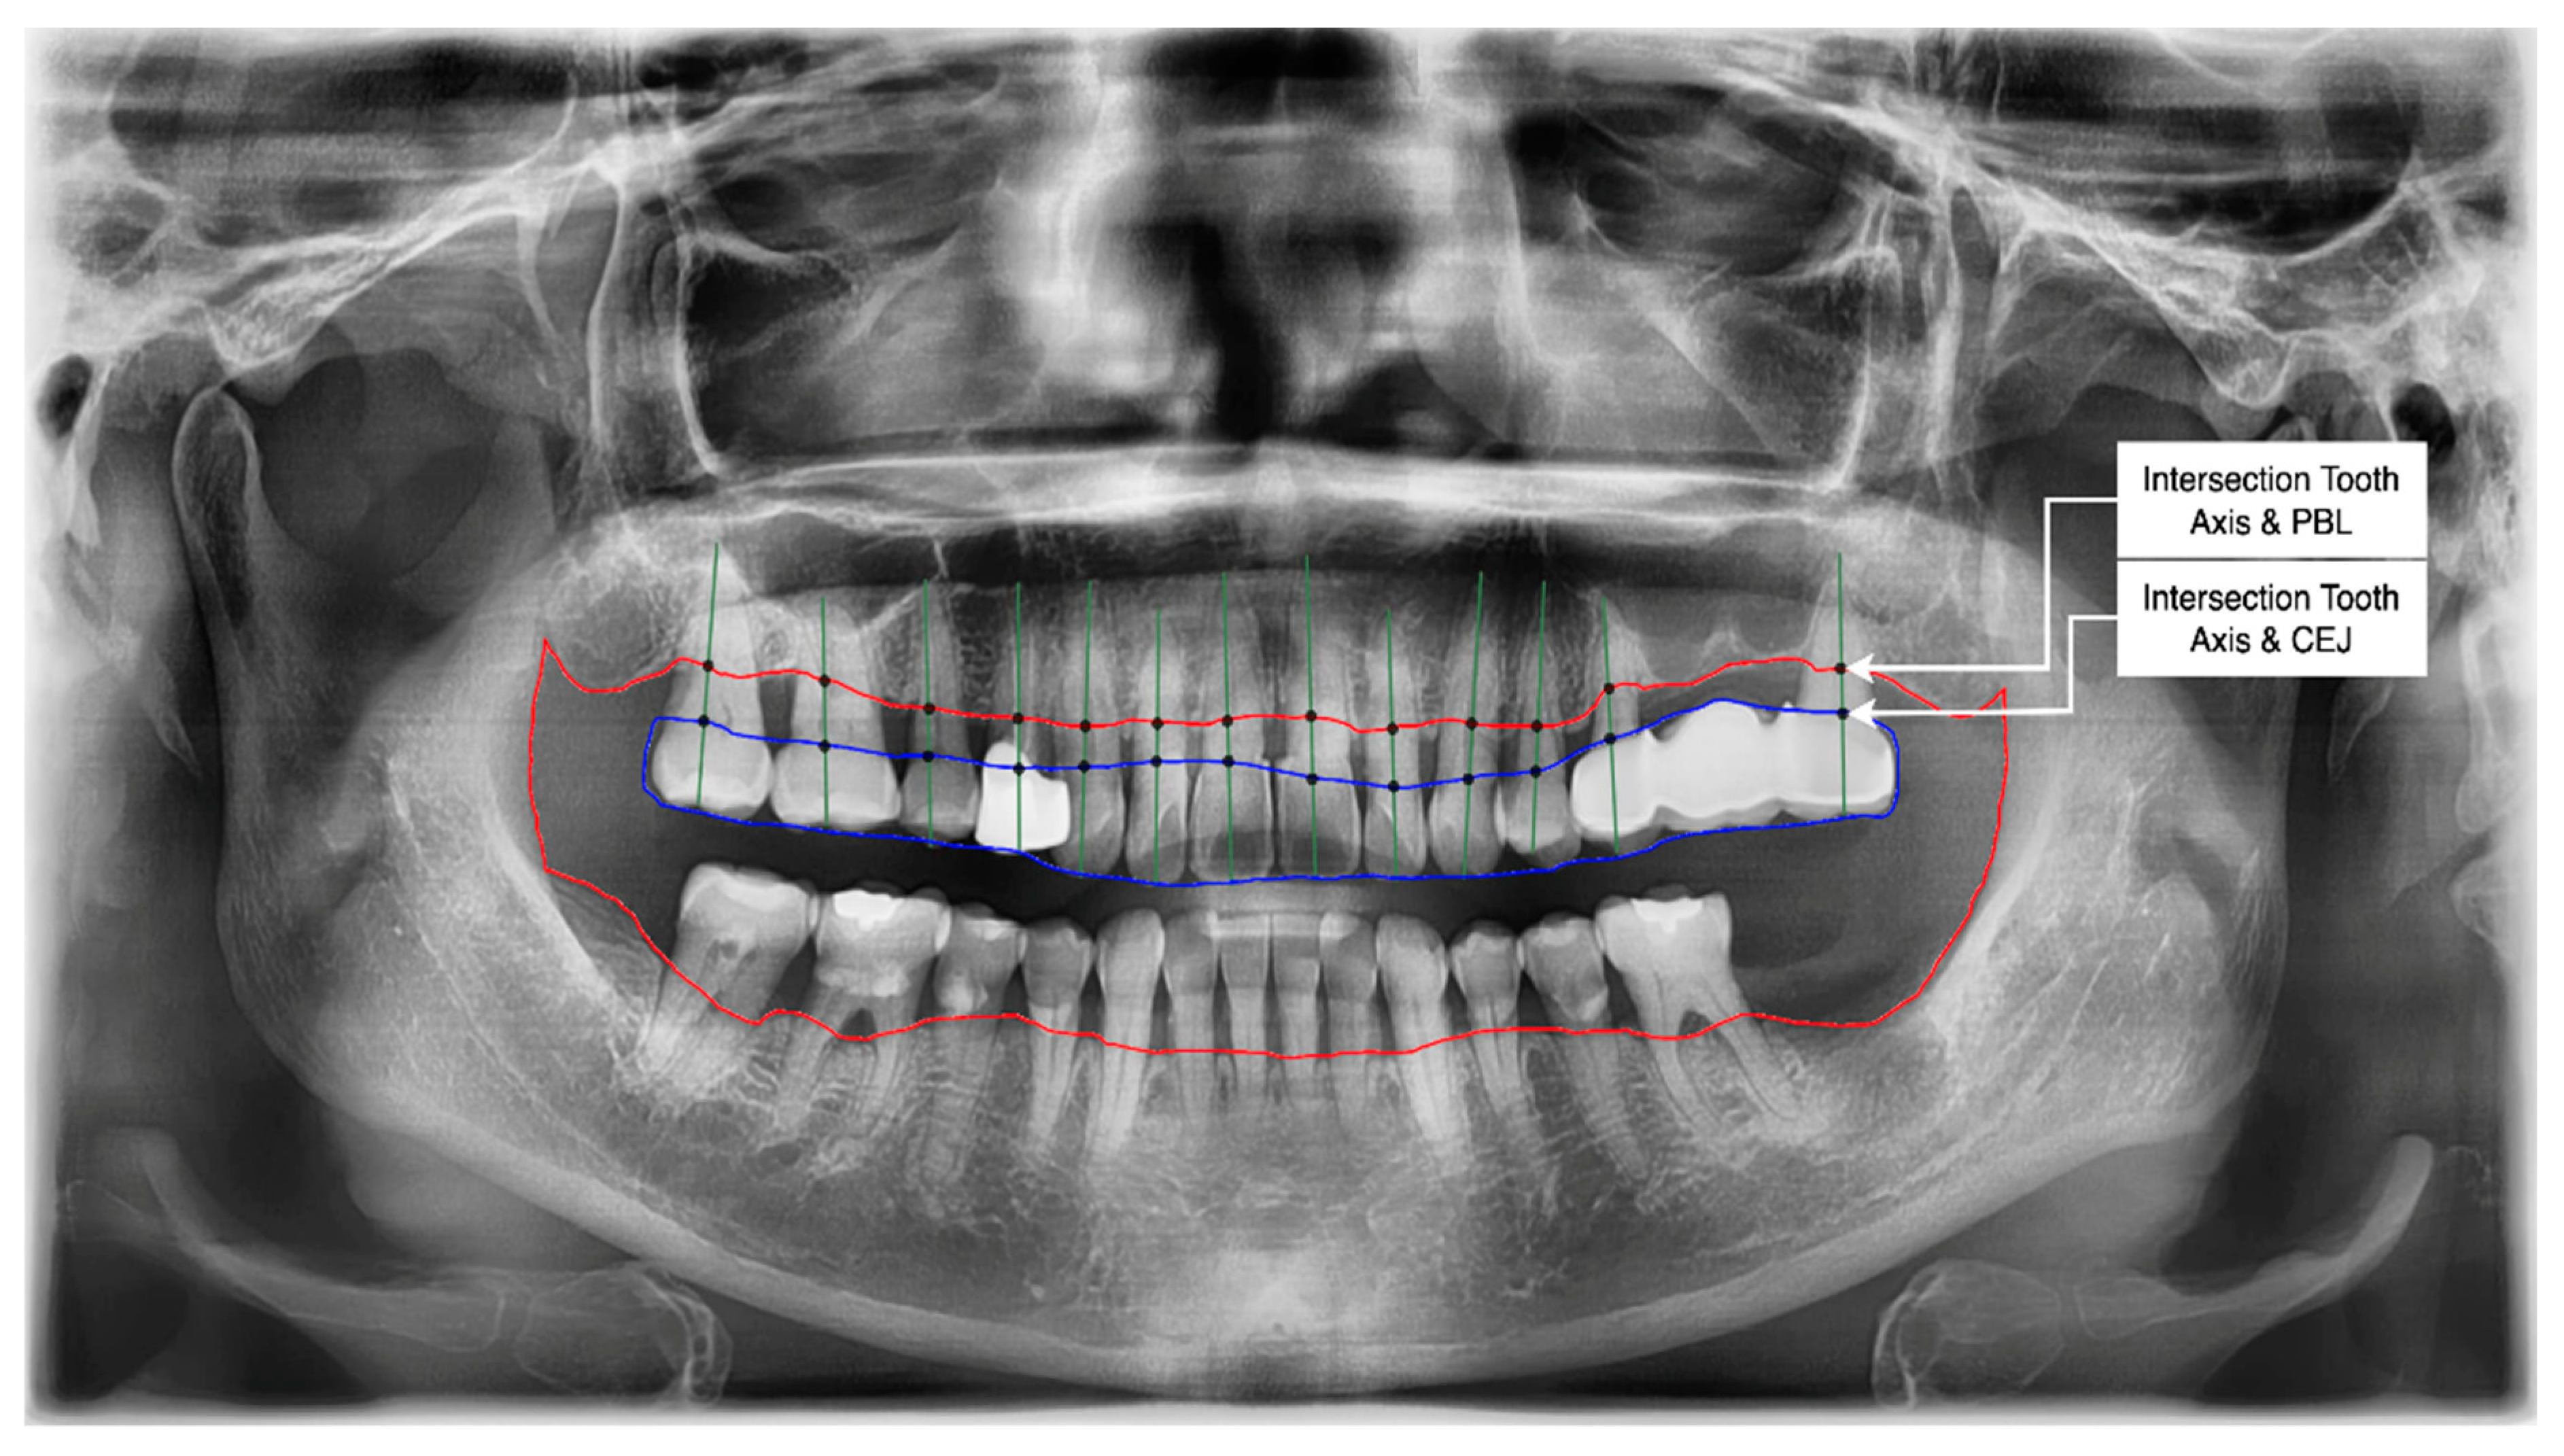

- Get the intersection of the PBL’s upper side and the tooth’s middle axis.

- Get the intersection of the CEJ’s upper side and the tooth’s middle axis.

- Calculate the length from those two intersections (known as the RBL length).

- Calculate the RBL percentage from the RBL length and tooth root.

3.4. Determination of Tooth Stage through U-Net and YOLOv5 Integration

Classification of the PBL by Percentage Rate Analysis